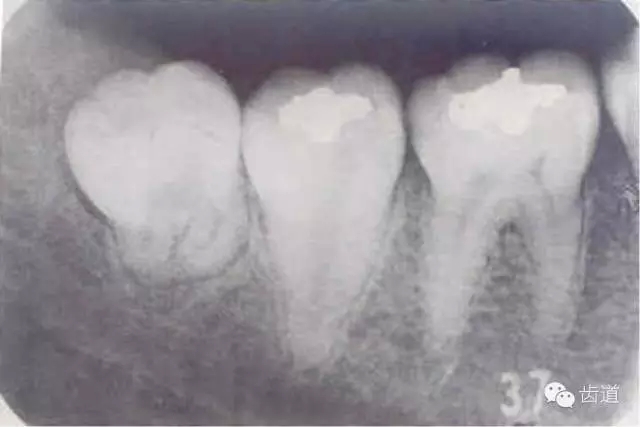

下頜第三磨牙在萌出過程中,由于萌出不全或阻生,牙冠周圍軟組織發(fā)生的炎癥。又稱智齒冠周炎。

1.人類進化過程中,下頜骨體逐漸縮短,導(dǎo)致第三磨牙萌出空間不足,表現(xiàn)為部分萌出、牙位偏斜甚至完全埋伏阻生

1.智齒萌出不全

2.牙冠周圍軟組織紅腫、糜爛、觸痛

3.齦瓣處形成盲袋,內(nèi)有膿性分泌物,有時形成冠周膿腫